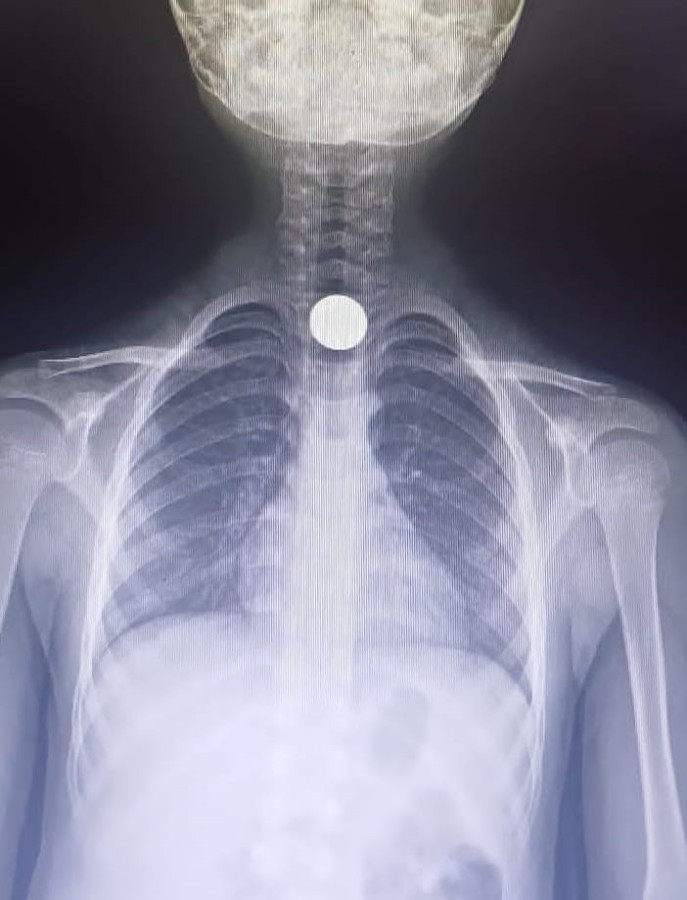

Parayı yutan Yusuf, bir anda fenalaştı. Durumu fark eden aile, çocuğu otomobille İnegöl Devlet Hastanesi'ne götürdü. Hastanede doktorlar tarafından yapılan tetkiklerde paranın yemek borusuna takıldığı tespit edildi.

Çocuk, boğazındaki paranın çıkarılması için Bursa Yüksek İhtisas Eğitim ve Araştırma Hastanesi'ne sevk edildi.